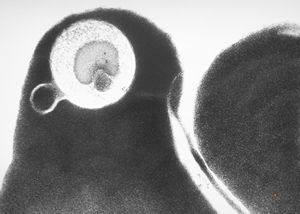

M,24y. | bone marrow - haemolytic anemia(ropalocyte - picturesque reticulocyte)

M,24y. | bone marrow - haemolytic anemia